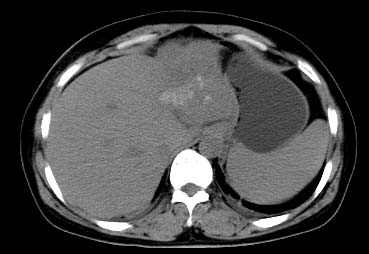

以下是引用西北一只狼在2008-6-30 20:58:00的发言:[br]肝左叶胆管细胞ca并肝门淋巴结转移、胰腺、胃小弯浸润

以下是引用ydx_74在2008-6-30 21:54:00的发言:[br]左叶胆管细胞ca并肝门淋巴结转移、胰腺、胃小弯浸润